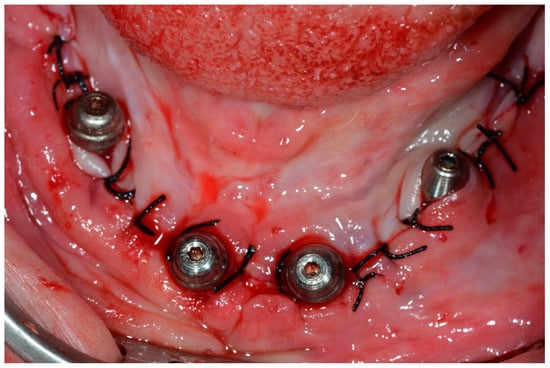

Implants with IT values equal to or higher than 75 Ncm were included in the study for follow-up and measurements, while implants with IT values lower than 75 Ncm were not marked as being of primary interest to this study. Despite this, when all four implants reached torques equal to or greater than 45 Ncm [22], immediate loading was performed. Straight multi-unit abutments were tightened to the anterior implants with a torque of 32 Ncm, and 17° or 30° angled multi-unit abutments (Dérig, São Paulo, Brazil) were drawn to the distal tilted implants with a torque of 20 Ncm [19]. After placing the abutments, the surgical wounds were sutured with 4-0 silk thread (Ethicon, São Paulo, SP, Brazil) (Figure 10).

Figure 10.

Occlusal view of the mandible after multi-unit covers were installed and sutured with 4.0 silk thread.